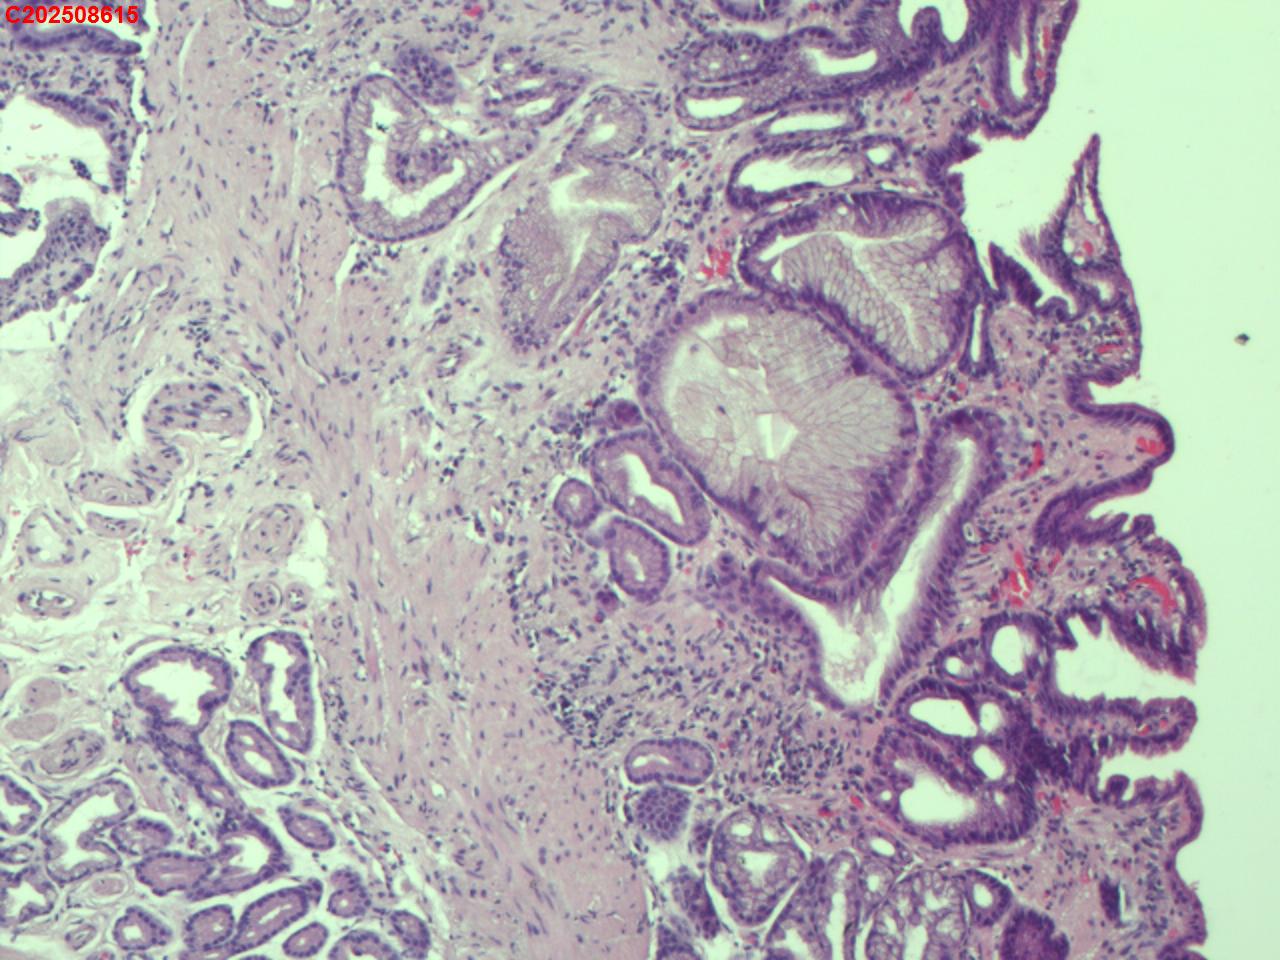

吻合口粘膜

性别

男

年龄

73岁

临床诊断

胃息肉、吻合口炎

一般病史

胃切除术后

标本名称

大体所见

吻合口处可见一枚直径约4mm息肉样隆起。

息肉样增生

这个形态如果在吻合口,可以考虑息肉样囊性胃炎。